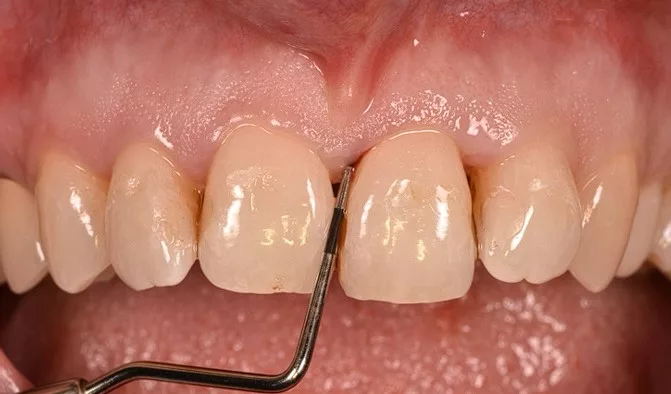

Réalisé lors de la première consultation, le bilan parodontal est basé sur un examen clinique et radiologique spécifiques.

Un bilan photographique

Un bilan photographique est réalisé afin d’enregistrer l’état initial. Il permet de communiquer avec le patient et les autres praticiens intervenant au cours du traitement (chirurgiens-dentistes effectuant les soins ou les traitements prothétiques, orthodontistes, endodontistes).

Ce bilan photographique sera renouvelé en fin de traitement.

Le sondage est réalisé à l’aide d’une sonde parodontale millimétrée. 6 mesures sont réalisées au niveau de chaque dent, 3 au niveau de la face avant et 3 au niveau de la face arrière.

Cet examen permettra de mesurer la profondeur des poches parodontales. La poche est l’espace formé entre la gencive et la surface de la dent par la maladie parodontale.